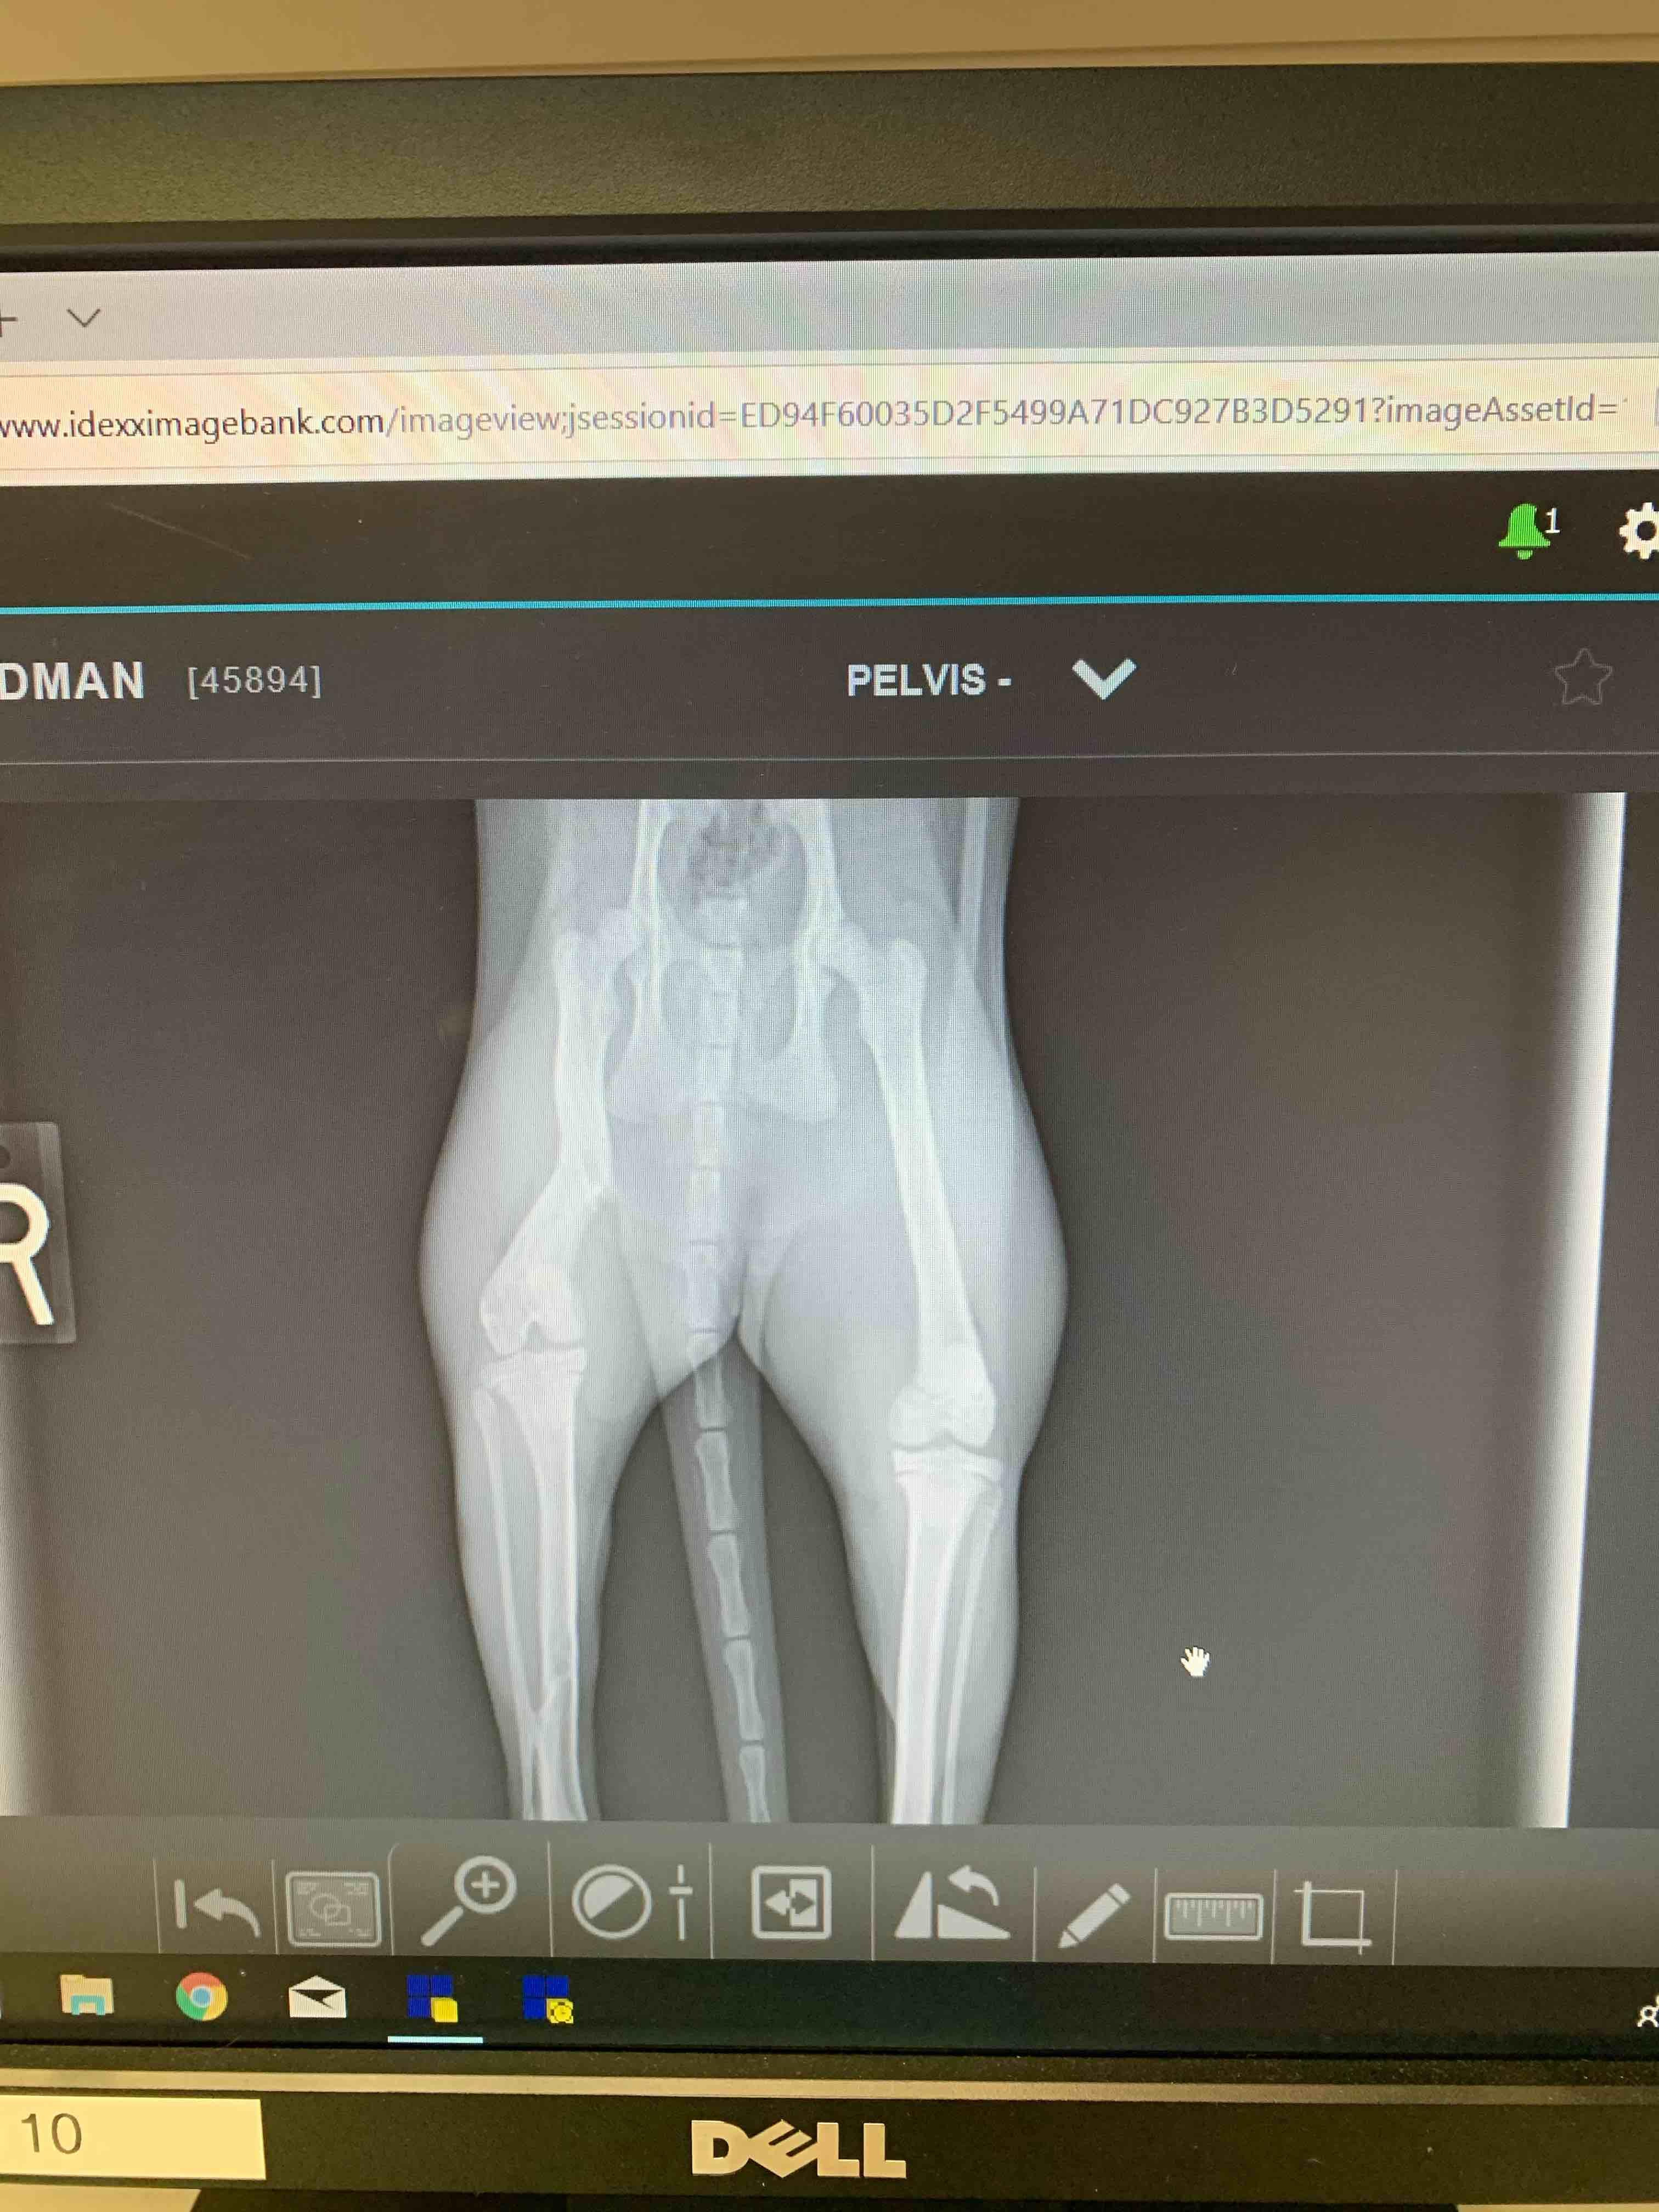

Her tibia & femur were fractured in May. She appeared to heal well until Oct 6. Now she limps a little, sits/lays with leg at odd angles, falls off of laps & furniture, cries out if picked up wrong, has reduced overall play a bit, keeps it still during play, uses it very lightly when jumping/running. Sometimes, she acts like nothing’s wrong. X-rays show misaligned knee, dislocated hip, badly healed femur. Vet #1 says amputate, #2 says no bc she’s using it. Amputate now while she’s small/young?

I think a third option might be available based on the x-ray - an FHO procedure to remove the ball of the femur and allow for more comfort with the dislocated hip. To me it sounds like Maggie is not using her leg much at all, and the vets don't think an FHO would help (which is certainly possible, I'm just suggesting based on what I can see in the x-ray) it sounds to me like amputation might be best. I would worry that she cries out because the leg is sometimes painful.